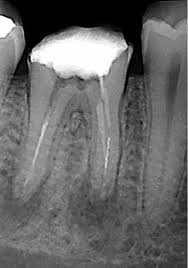

Modern medicine aims to work on two principles viz. prevention and regeneration and endodontics is no exception. In 2007, the Journal of Endodontics published a “call to action” article urging scientists, endodontic professionals, and funding agencies to hasten the development of research in this field of regenerative endodontics. Ever since, this field has received enormous attention from researchers and clinicians. Existing literature shows that both mineral trioxide aggregate (MTA) apical plug (MAP) and regenerative endodontic treatment (RET) have shown acceptable clinical outcomes in immature teeth affected by pulp and the periapical diseases. However, high quality studies directly comparing the outcomes of MAP and RET are scarce. Hence, this Randomized clinical trial aims to compare the clinical and radiographic outcome (using CBCT) of apexification and RET using injectable PRF.

A prospective pre and post interventional comparative study involving patients with a clinical diagnosis of moderate-to-severe chronic periodontitis is being carried out in the department of periodontitis. Inclusion criteria included presence of a 3-walled infrabony defect (IBD) ≥ 3 mm deep in which depth is measured radiographically from the alveolar crest to the base of defect on an intraoral radio-visiographical (RVG) periapical radiograph and the architecture of the 3-walled IBD is confirmed upon surgical exposure of the defect.